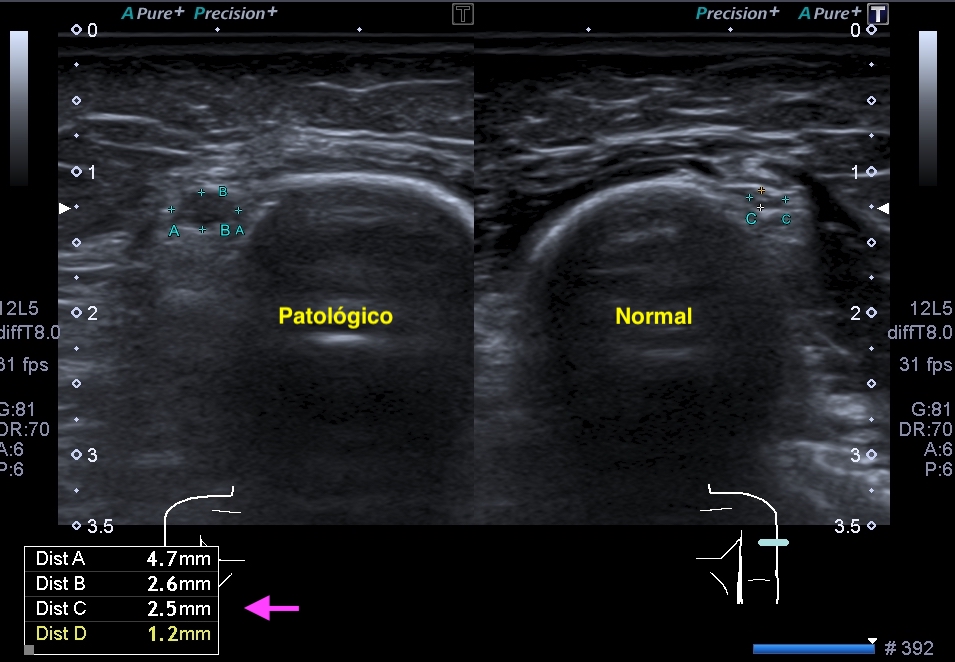

La radiografía revela aumento de las partes y se refrenda en la ecografía como puedes ver en la imagen aunque aún no hay afectación en el hueso en el caso que te presento hoy.

Ecografícamente y debido a su levedad, en el caso de hoy solo observamos cambios en las partes blandas de la cara lateral de la cabeza del quinto metatarsiano, este tejido se muestra heterogéneo, la cortical del hueso ligeramente prominente sin afectación de la misma.